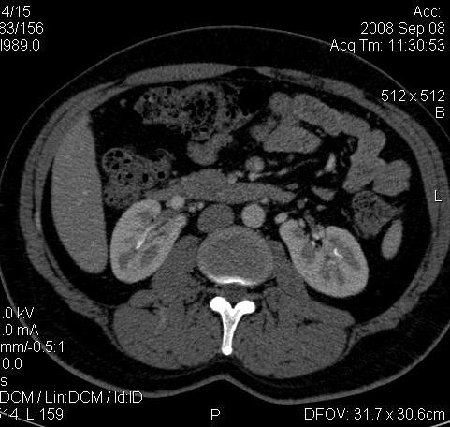

КТ Почек- подкова и уретеролитиаз

Данное наблюдение весьма демонстративно само по себе.

Ну ладно, раз никто больше не хочет, то отвечу свою версию - аномалия развития - подковообразная почка (horseshoe kidney).

Да красивая подковообразная почка - встречала раз 6-7.

Не вызывает сомнений. Картинка замечательная. Должно быть хорошо видно и на УЗИ.